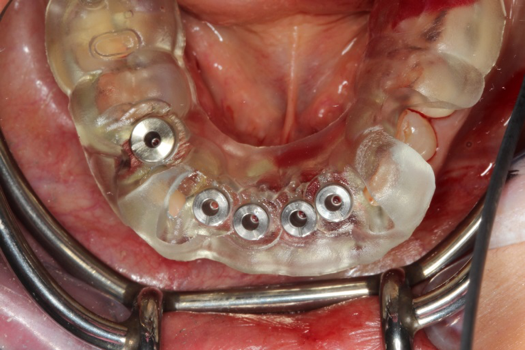

The next case follows the digital protocol for fully guided surgery and prosthetics. A CBCT radiograph, digital impression, and digital photography were the cornerstones to the success of this case. The 3D data set was electronically delivered to the dental laboratory. The data were merged and the process to develop the plan was initiated. The use of CBCT was essential in this case, particularly due to minimal space for placement of individual implants and single-unit crowns. The patient's chief concern was that she wanted to have single-unit crowns instead of fixed crown-and-bridge restorations because she was worried that she would someday find herself in an assisted-living facility; if that were to happen, she wondered, who would help floss under her bridge work? Her decision was to have single implants with individual crowns. CBCT technology is much more accurate in evaluating space maintenance and management.10 Periapicals in the past were rather close for calculating spacing; however, the CBCT identifies the buccal-lingual dimensions as well as the mesial-distal measurements. On review of the completed proposals for implant placement and provisionals, it was determined that there was sufficient spacing for implant placement to allow appropriate emergence profiles for the provisionals and then eventually the final single-unit cemented crowns. The proposal was accepted, and a 3D-printed surgical stent was fabricated, along with the PMMA provisionals (Figure 29 through Figure 35).

Fig 42. Occlusal view of prepared implants.

Figure 42